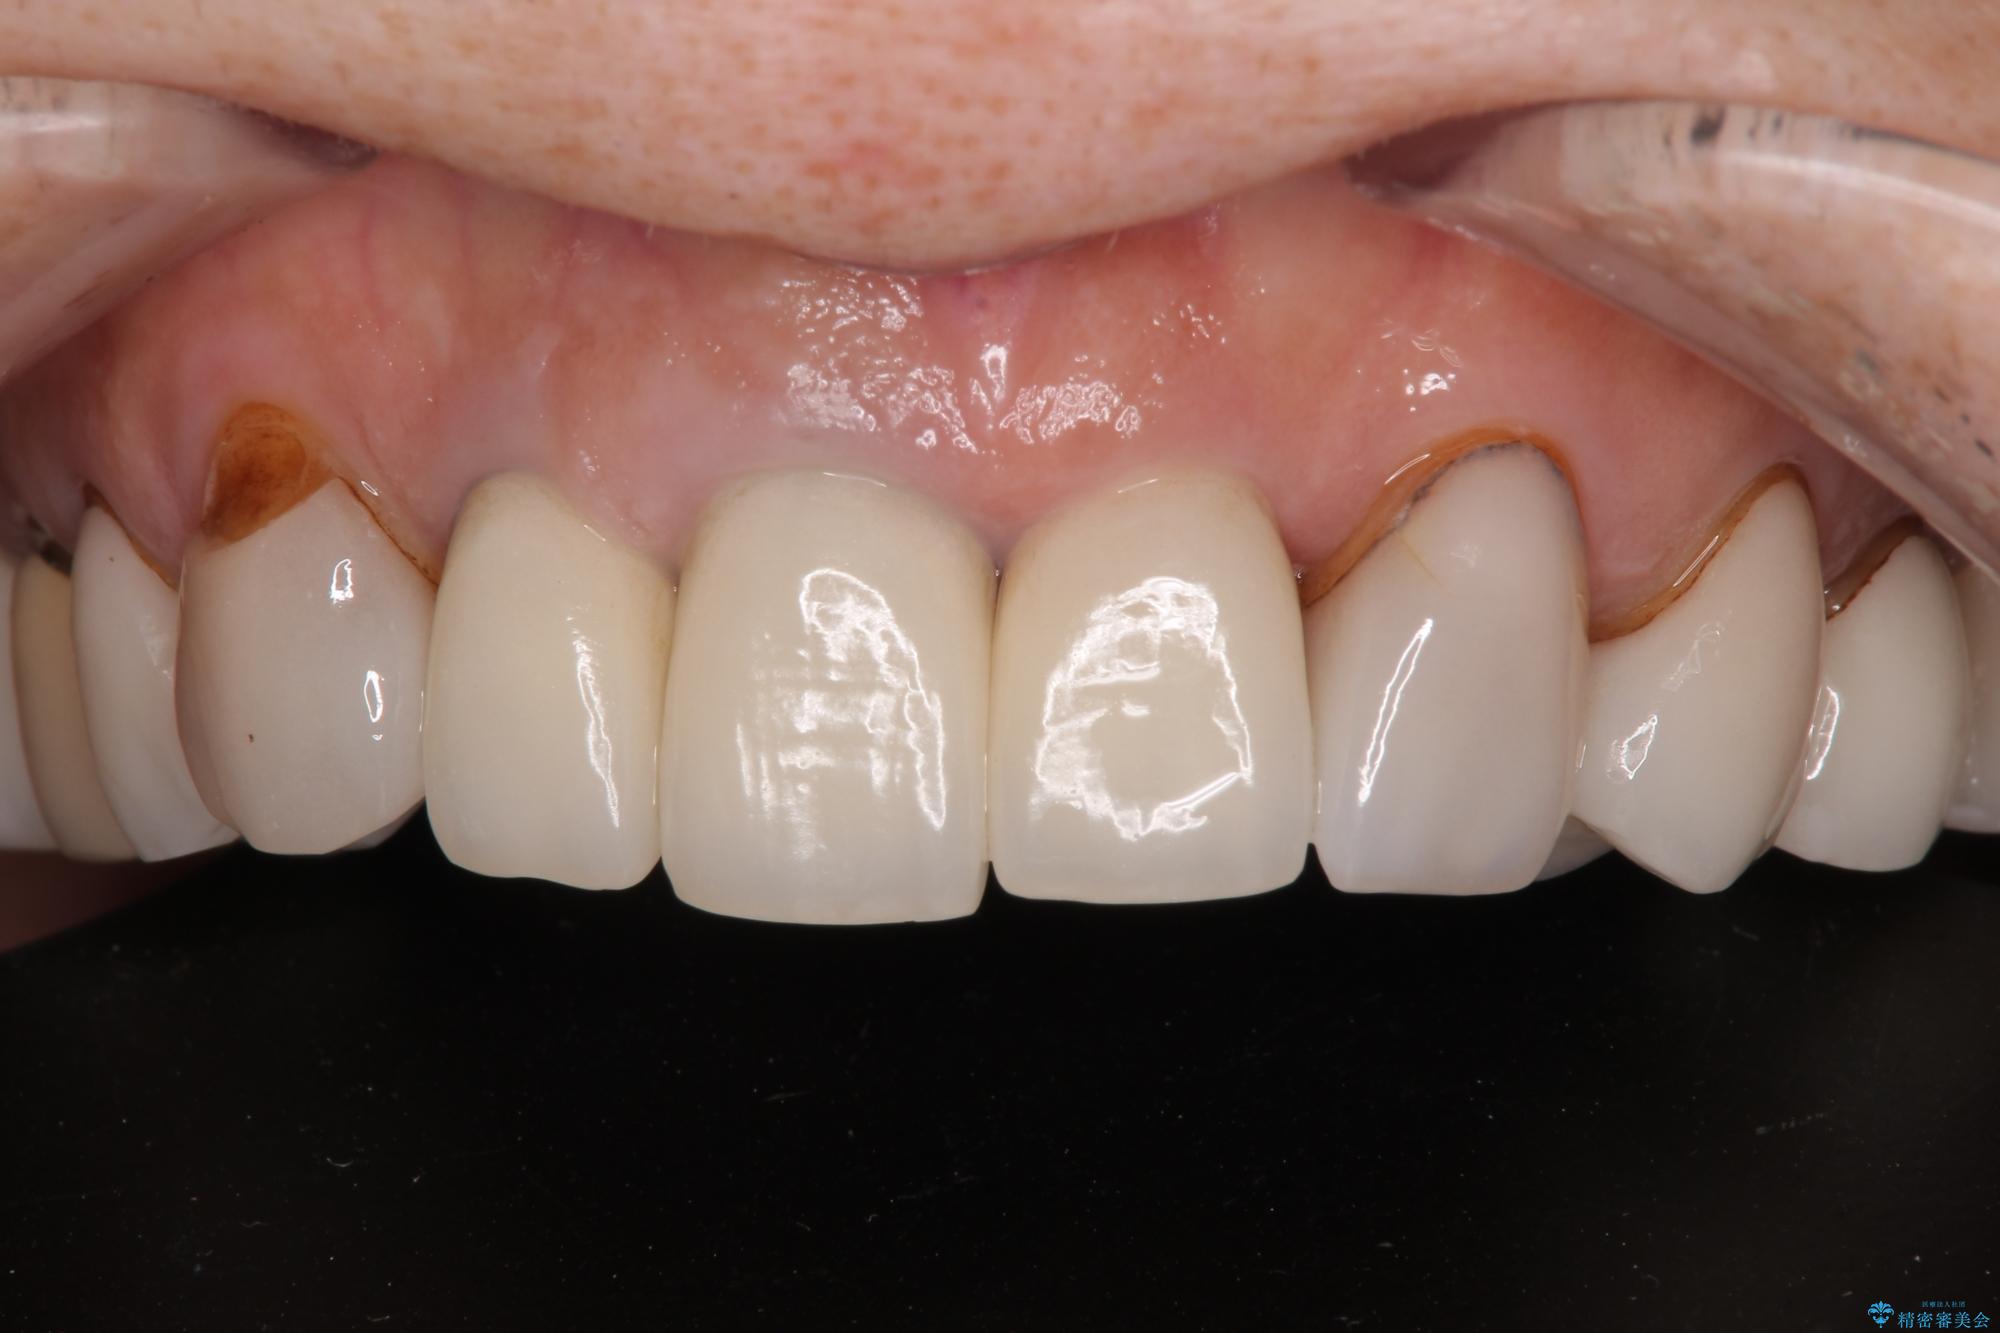

色調が統一されるだけでなく、歯肉ラインに見えていた茶色の境目も綺麗に改善されました。

20年以上前から、むし歯になったり詰め物が欠けたりする度に部分的に処置を行ってきたそうですが、この際統一感のある前歯にしたいとのことで、上顎前歯9本をオールセラミッククラウンによる補綴治療を行うこととしました。